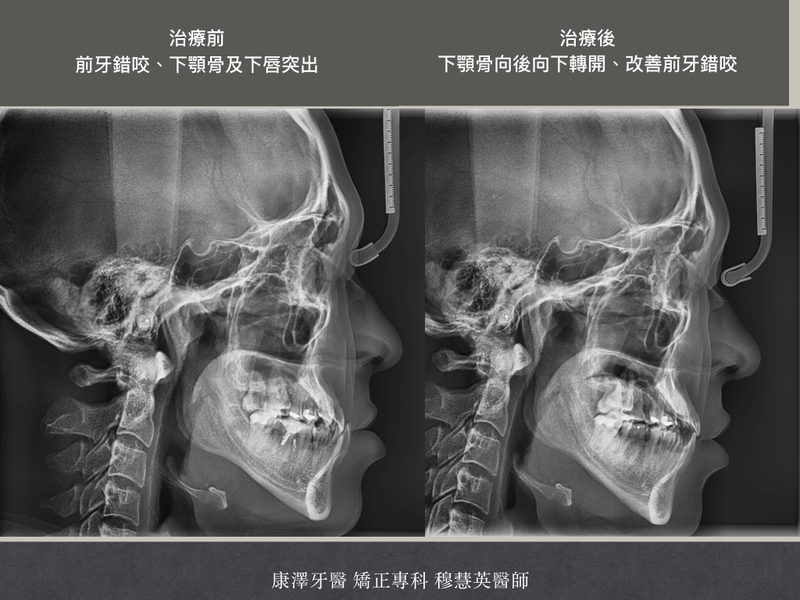

今天要分享一位成年男性的矯正案例,在林口康澤牙醫矯正專科穆慧英醫師的診療下,他透過隱形矯正成功改善戽斗、深咬、下唇突出與齒列不整齊,不僅找回了理想臉型,還意外成功戒菸!

患者是一位成年男性,長期受到以下問題困擾:

✅ 戽斗(下顎前突),導致臉部比例不協調

✅ 深咬(下排牙齒過度覆蓋上排牙齒),影響咀嚼與發音

✅ 下唇突出,讓側臉線條不流暢

✅ 齒列不整齊,影響美觀與清潔

除了外觀影響,這些問題也讓他的咬合與發音受到影響,因此他決定勇敢踏上矯正之路!

✅ 戽斗改善,臉型更和諧

✅ 下唇回收,側臉線條更好看

✅ 深咬問題解決,咀嚼更順暢

✅ 齒列整齊,笑容更加自信